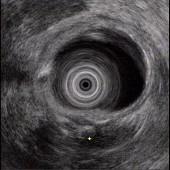

问题 男性,44岁反复上腹钝痛2年余伴纳差,超声内镜如图,胰腺病变可能的诊断是 ( )

选项 A.正常 B.胰腺囊肿 C.慢性胰腺炎 D.胰腺囊腺癌 E.胆总管结石伴扩张

答案 C